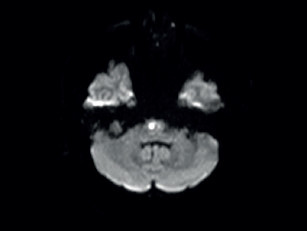

Potíže se začátkem roku 2019 opakovaly a přidala se k nim porucha časové orientace a pracovní paměti, pro což byl odeslán k akutnímu vyšetření v naší ambulanci. Pacient potíže negoval. Při neurologickém vyšetření byl klidný a orientovaný všemi modalitami. Působil zpomalenějším dojmem. Řeč byla plynulá, slovní projev měl normální. Nevykazoval známky kognitivní poruchy, neurotopický nález byl v normě. Vyšetření pomocí CT mozku prokázalo nespecifické změny bílé hmoty paraventrikulárně a subkortikálně (obr. 1). Vyšetření pomocí elektroencefalogramu (EEG) bylo normální. U pacienta byla zahájena léčba ASA v dávce 100 mg 1× denně a atorvastatinem v dávce 40 mg 1× denně. Dle MR mozku (únor 2019) byly přítomny změny bílé hmoty obou mozkových hemisfér charakteru splývající gliózy, která postihovala i pons. Dalším nálezem byly lakuny v bazálních gangliích, více vpravo (obr. 2). Dle radiologa obraz nejvíce připomínal Binswangerovu nemoc. Pacient se vyučil a v poslední době pracoval ve 12hodinovém směnném provozu jako řidič nákladního vozu na šachtě. Vojenskou prezenční službu absolvoval bez omezení. Úraz hlavy neprodělal. Nekouřil, denně vypil 1–2 piva. Dlouhodobě užíval alopurinol pro dnavou artropatii. Sledovaná interní a neurologická onemocnění negoval. V rodinné anamnéze stojí za zmínku náhle úmrtí otce v 59 letech (nalezen na chodníku), příčinu úmrtí neznal. Matka a synové jsou zdrávi. V rodině není zaznamenán výskyt neurologického nebo psychiatrického onemocnění. V březnu 2019 byl pacient přijat na naše oddělení pro smíšenou afázii, která v době přijetí trvala déle než 8 hodin. Další neurologický deficit přítomen nebyl. Vstupní CT mozku neprokázalo akutní změny v terénu splývajících hypodenzních změn v supratentoriální bílé hmotě oboustranně. CT angiografie (CTA) mozkových tepen ani neurosonologické vyšetření neprokázaly významnější patologii na extrakraniálních i intrakraniálních tepnách. Biochemické vyšetření séra potvrdilo hyperurikemii a hyperlipidemii, jiné abnormality přítomny nebyly. Glykemický profil byl normální. Vstupní hodnoty krevního tlaku byly mírně zvýšené (140–160/90–100 mm Hg), spontánně se během 24 hodin upravily do normotenzních hodnot. Vstupní EKG bylo normální a i monitorace EKG včetně Holterova monitorování EKG neodhalily srdeční arytmii. EEG bylo abnormní pro pomalou aktivitu theta a delta frontotemporálně vpravo. Sérologický test na syfilis, onkomarkery, onkoneurální protilátky a laboratorní testy na vaskulitidy byly negativní. Během 48 hodin se fatická porucha plně upravila. Pacient sděloval, že se cítí dobře a nemá žádné potíže. Na vlastní žádost (negativní revers) byl propuštěn do domácí péče. K vyšetření trombofilních stavů se nedostavil. Po opakovaném odložení ze strany pacienta bylo v dubnu 2019 doplněno vyšetření mozkomíšního moku z lumbální punkce. Zjištěna lehce zvýšená hodnota bílkoviny (0,68 g/l) a hraniční lymfocytární pleocytóza s přítomností výraznější aktivity v monocytární řadě. Cytologický nález byl v normě. Absence známek intratekální oligoklonální syntézy imunogobulinů G, A, M (IgG, IgA, IgM) a volných lehkých řetězců (FLC) kappa/lambda nesvědčily pro demyelinizační onemocnění typu sclerosis multiplex. Absence protilátek IgG proti aquaporinu 4 v krvi vylučovaly neuromyelitis optica. Koncentrace tau proteinu byla normální. Protein 14‑3‑3 byl negativní. Neuroborelióza byla vyloučena. S odstupem bylo provedeno kontrolní vyšetření mozku pomocí MR, ve srovnání s předchozím vyšetřením však neodhalilo nové změny. MR angiografie (MRA) mozkových tepen zobrazovala normální nález na intrakraniálních tepnách. Další vyšetření včetně genetického pacient neakceptoval.